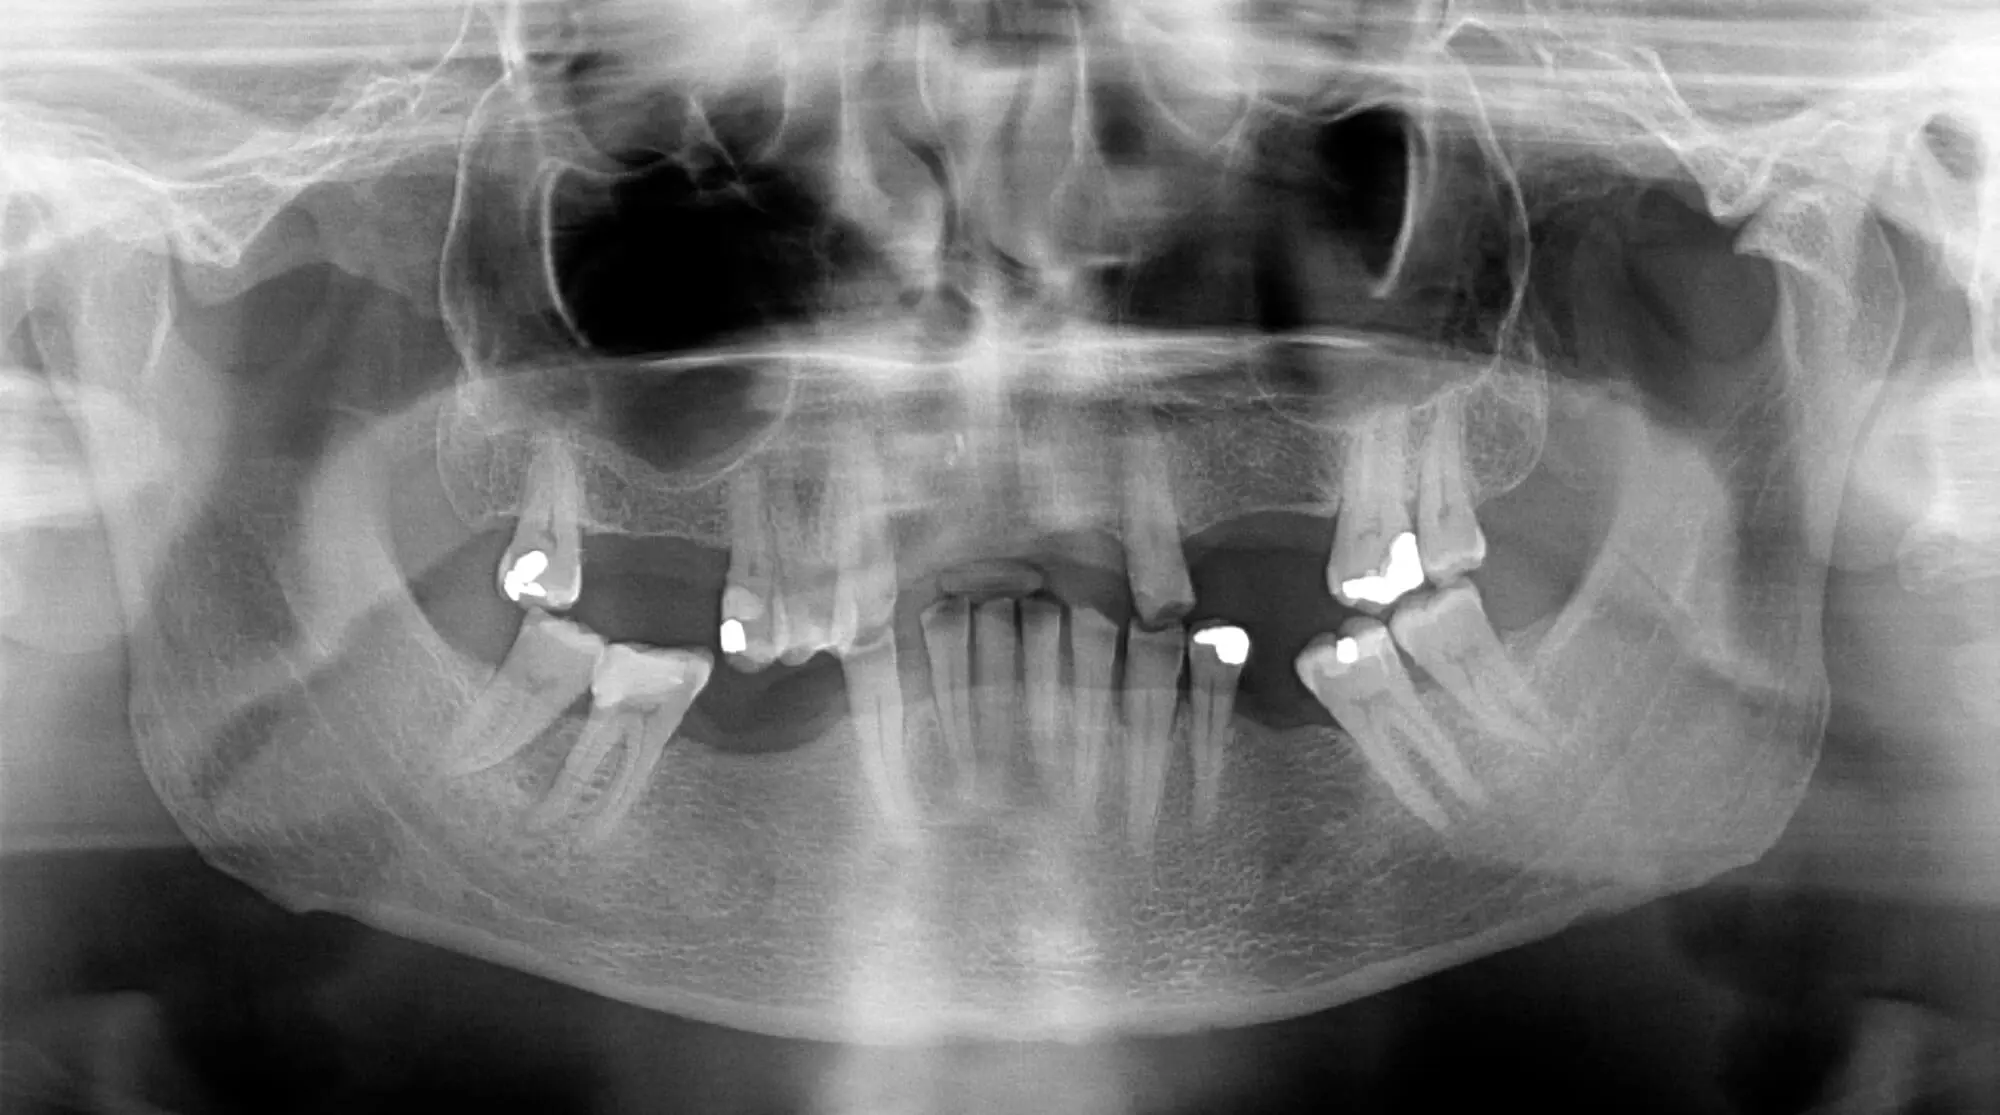

2. Your Other Teeth Begin to Shift

When a tooth goes missing, your other teeth don’t stay in place. They start drifting toward the space, throwing off your alignment and creating new gaps or crowding.

This can misalign your previously perfect smile and cause increased wear and tear on healthy teeth.